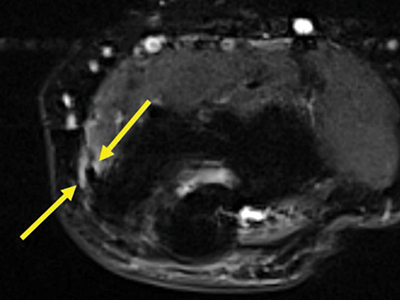

Materials and methods: Two hundred and five magnetic resonance imaging (MRI) exams of the elbow with coronal and axial fat-saturated fluid-sensitive sequences between January 1, 2018 and July 31, 2022 were retrospectively identified in our center.Two radiology residents reviewed the exams independently. The elbow tendons were given a score from 0 to 4. Score 0: no signal abnormality; score 1: increased T2-weighted signal around the tendon; score 2: increased T2-weighted signal compared to muscle within the tendon; score 3: partial tear; and score 4: complete tear.

Results: The common flexor tendon showed signal alterations in 8% of patients; nine patients had an increased signal around the tendon, and eight patients had an increased signal within the tendon. Three patients (1.5%) had an altered signal intensity in the biceps tendon. All triceps tendons showed a linear hyperintense signal, suggesting that it is physiological. There were no partial or complete tears. No signal abnormalities were noted in the brachialis tendon among all patients.

Abstract Image